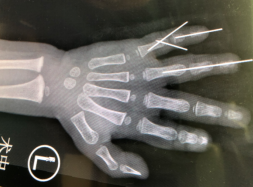

医院立刻为优优开通了绿色通道,接到通知的手外科三病区的吴尧医生先为优优做了检查,检查发现优优的左手环指两段离断(一段完全离断,一段不完全离断),优优的血管挫伤较重,血管条件非常不好。但优优的家人保指意愿非常强烈,孩子还这么小,手指一根都不能少啊!

吴尧、吴贞志医生团队确定手术方案后,为小优优进行了再植手术,术中在高倍显微镜下小心吻合断裂的血管、神经和肌腱。吻合度越高,小优优才能恢复得更快更好。这场手术的难度绝不亚于任何多指离断再植的难度,因为两段离断手术再植难度是单指离断的数倍,而小优优又是绞伤,血管条件十分差,这对外科医生来说无疑是个大挑战。家长看着手指接上的孩子被推出手术室,激动地哭了。